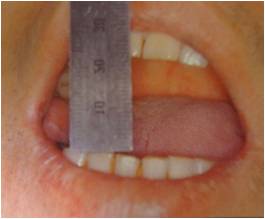

설통(Glossodynia)

증상

미각이상

,

작열감

혀의 통증

관련질환

삼차 신경병증

진료과

이비인후과

치과